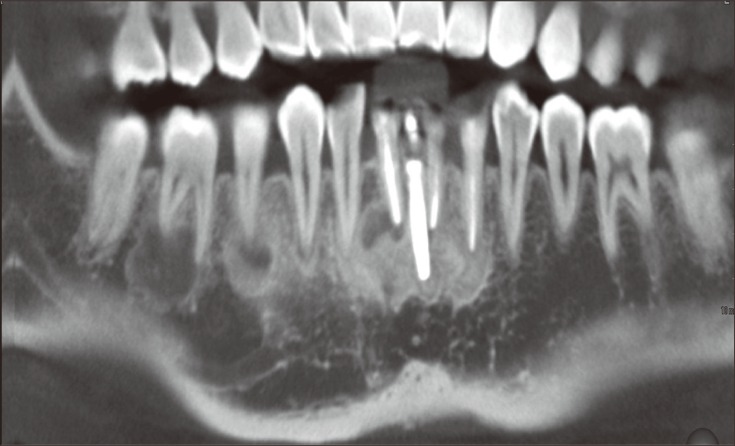

Figure 3

Computed tomography (CT) images at the initial visit. (a) A panoramic reconstruction of the CT images at the level of the apices. Multiple lesions bony lesions were detected; (b) Axial images of #42, 32, and 46 at the apical level. Mixed radiopaque and radiolucent lesions as well as cortical bone perforation were observed; (c) Vertical images showing thinning and perforation of the cortical plate without any expansion.

In the periapical areas of #32, 33, 36, 42, 43, 45, 46 and the implant, lobular-shaped radiolucencies that contained small radiopaque masses were revealed by computed tomography (CT, Somatom Sensation 64, Siemens, Munich, Germany, 120 Kvp, 90 mA). All of the lesions were related to the cortical plates, and perforation of labial and lingual cortical bones was observed on the mandibular lateral incisors. No cortical bony expansion was detected (Figure 3). Periapicies of maxillary teeth were examined as normal condition.